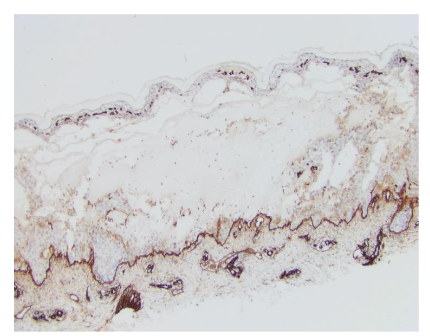

The best-known cutaneous manifestation associated with CeD is dermatitis herpetiformis, also known as Duhring-Broque Disease. It is present in > 85% of those with CeD and improves with a gluten free diet. Both DH and CeD hold a well characterized association with HLA DQ2 and DQ8. These genes are present in 85% of patients with DH vs 25% of controls. First degree relatives with DH have an increased risk of DH and CeD. As with CeD, there is an association with autoimmune thyroiditis, type 1 diabetes mellitus and the risk of lymphoma. Patients with DH do not always have gastrointestinal symptoms, but in duodenal biopsy, 75% of patients diagnosed with DH had varying degrees of villous blunting, which is characteristic of CeD, emphasizing the marked correlation between the two phenotypes. After gluten ingestion, gliadin is absorbed and crosslinks with tissue transglutaminase in the intestine. Ultimately, antibodies form against tissue transglutaminase. Via epitope spreading, these antibodies become capable of binding to epidermal transglutaminase. These IgA antibodies deposit in the papillary dermis due to their greater affinity for epidermal transglutaminase than tissue transglutaminase. This causes inflammation at the site of IgA aggregation and recruitment of neutrophils, leading to microabscesses.